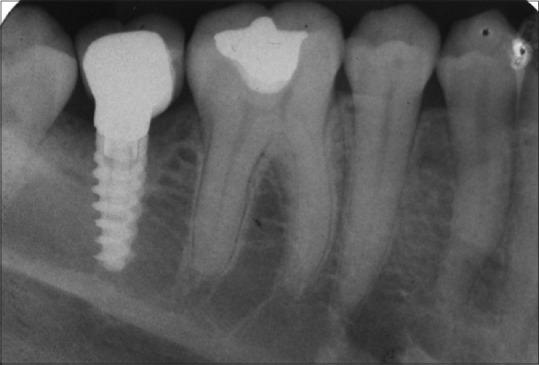

Vitamin D has been shown to play a vital role in bone mineral homeostasis by stimulating the intestinal absorption of calcium and phosphate. The critical role of Vitamin D in bone metabolism triggered the need to evaluate the effect of Vitamin D deficiency and hence replacement of the same on osseointegration of dental implants. This prospective study evaluated the crestal bone level in patients having low level of Vitamin D treated with dental implant with or without Vitamin D3 supplements.

MATERIALS AND METHODS

A prospective clinical study was conducted on 32 patients based on the inclusion and exclusion criteria. Patients were divided into two groups on the basis of Vitamin D level < 30 ng/ml (Group I: patients receiving Vitamin D3 supplements, i.e., cholecalciferol 1 g sachet 60,000 IU/month) or <30 ng/ml (Group II: not receiving Vitamin D3 supplements). The crestal bone level measurements were made with the help of Digimizer Image Analysis, MedCalc software.

RESULTS

All implants showed clinically acceptable crestal bone level at interval of 1 week (baseline), 3 months, and 6 months. There was a statistically nonsignificant difference seen for the values between the groups ( > 0.05) for all other values at various time intervals. However, there was a statistically significant/highly significant difference seen for the values between the groups ( < 0.01, 0.05) for 3 months distal with higher values for Group I as compared to Group II.

CONCLUSION

From the study, it can be concluded that cholecalciferol has systemic effects on accelerating bone formation around titanium implant.

维生素D已被证明通过刺激肠道对钙和磷的吸收,在骨矿物质稳态中发挥至关重要的作用。维生素D在骨代谢中的关键作用引发了评估维生素D缺乏的影响以及补充维生素D对牙种植体骨整合影响的需求。这项前瞻性研究评估了接受或未接受维生素D3补充剂治疗的维生素D水平低的患者种植体周围嵴顶骨水平。

材料与方法

根据纳入和排除标准,对32例患者进行了一项前瞻性临床研究。根据维生素D水平<30 ng/ml将患者分为两组(第一组:接受维生素D3补充剂,即胆钙化醇1 g小袋,60,000 IU/月)或<30 ng/ml(第二组:未接受维生素D3补充剂)。借助Digimizer图像分析软件MedCalc进行嵴顶骨水平测量。

结果

所有种植体在1周(基线)、3个月和6个月时均显示出临床上可接受的嵴顶骨水平。在各个时间间隔的所有其他值中,两组之间的值存在统计学上无显著差异(>0.05)。然而,在3个月时,两组之间的值存在统计学上的显著/高度显著差异(<0.01, 0.05),第一组的值高于第二组。

结论

从研究中可以得出结论,胆钙化醇对加速钛种植体周围的骨形成具有全身作用。